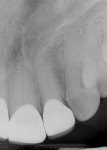

The restorations were delivered a few weeks later. Prior to cementation, marginal integrity of the restorations was reviewed. The author's protocol for approval of restorations for final delivery includes tactile and radiographic evaluation of the margins (Figure 8 and Figure 9). Once the restorations are approved for marginal integrity, occlusion, contacts, and esthetics, the process of isolation and cementation is begun. In this case, it was decided to cement the restorations with resin-modified glass-ionomer cement (RMGIC) (GC FujiCEM® Evolve, GC America, gcamerica.com). The long-term stability of using RMGIC to cement zirconia-oxide restorations, especially for preparations of teeth demonstrating an adequate resistance and retention form, has been shown to be effective in preventing premature loss of restoration and microleakage.10